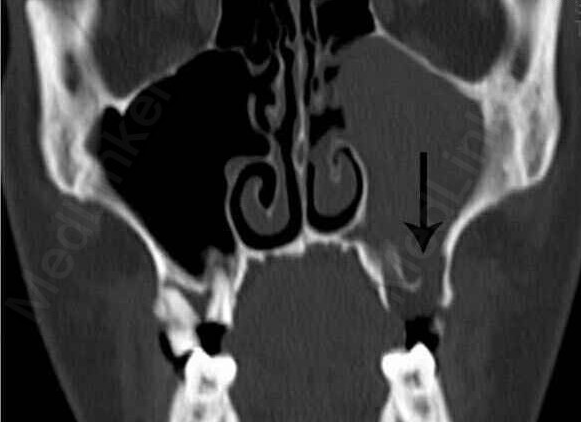

李女士看完牙之后接着就到了耳鼻喉科。接诊的济南市第一人民医院耳鼻喉科主任高克梁经过详细检查,初步判断李女士是牙源性上颌窦炎,并建议李女士拍一个鼻窦的CT以确诊自己的判断。

鼻窦CT的结果与高主任的判断一致,果然是牙源性上颌窦炎。高主任向李女士介绍牙源性上颌窦炎引起鼻腔异味的原因。